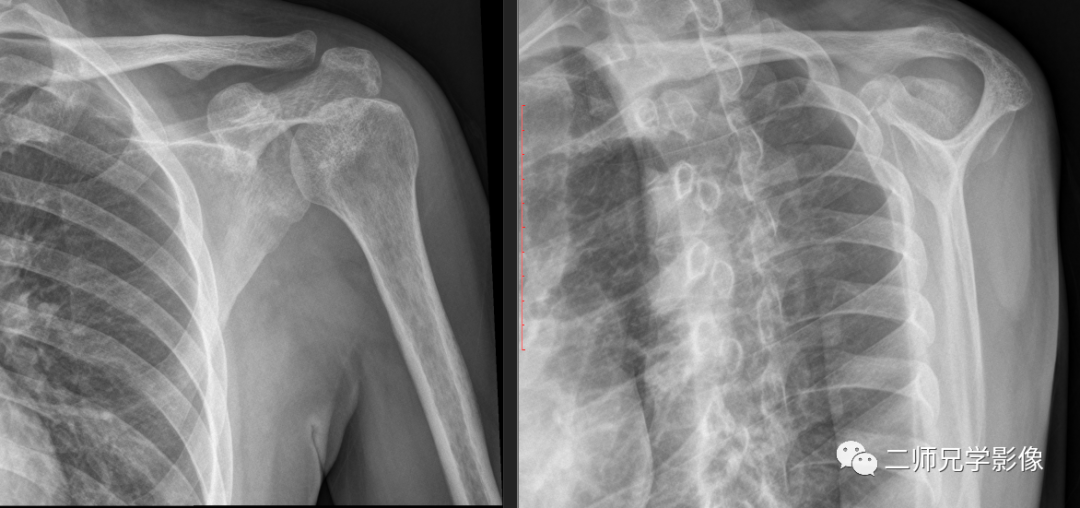

图六:拍摄肩胛骨时,从不同的位置和角度拍摄,显示出不同的影像

怎么取放射片放射拍片中的“几何学”,临床医生和技师都掌握了吗?_https://www.jmylbn.com_新闻资讯_第9张

以上前五幅图片(图一至图五)就是从不同角度去拍摄不同物体,显示出不同的影像。同样,我们放射科拍片时也是一样的,同一个身体部位,从不同角度去拍摄,就会显示出不同的影像(图六图七)。